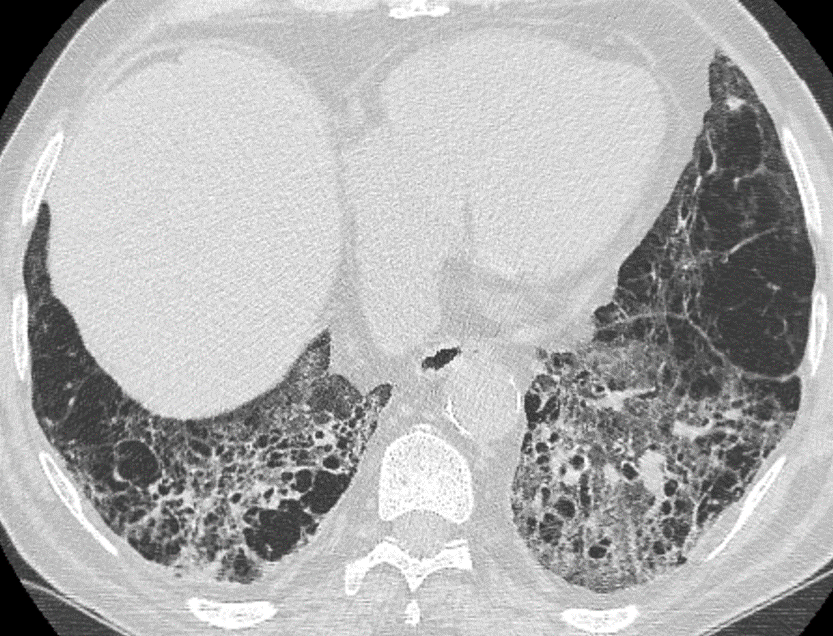

Lung fibrosis

Lung fibrosis can be qualitatively graded into three levels: 0-10%, 11-30%, and > 30%. Usual interstitial pneumonia (UIP) and nonspecific interstitial pneumonia (NSIP) are the main CT patterns of lung fibrosis.